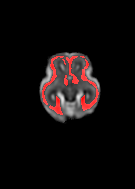

Fetal cortical plate segmentation is essential in quantitative analysis of fetal brain maturation and cortical folding. Manual segmentation of the cortical plate, or manual refinement of automatic segmentations is tedious and time-consuming. Automatic segmentation of the cortical plate, on the other hand, is challenged by the relatively low resolution of the reconstructed fetal brain MRI scans compared to the thin structure of the cortical plate, partial voluming, and the wide range of variations in the morphology of the cortical plate as the brain matures during gestation. To reduce the burden of manual refinement of segmentations, we have developed a new and powerful deep learning segmentation method. Our method exploits new deep attentive modules with mixed kernel convolutions within a fully convolutional neural network architecture that utilizes deep supervision and residual connections. We evaluated our method quantitatively based on several performance measures and expert evaluations. Results show that our method outperforms several state-of-the-art deep models for segmentation, as well as a state-of-the-art multi-atlas segmentation technique. We achieved average Dice similarity coefficient of 0.87, average Hausdorff distance of 0.96 mm, and average symmetric surface difference of 0.28 mm on reconstructed fetal brain MRI scans of fetuses scanned in the gestational age range of 16 to 39 weeks. With a computation time of less than 1 minute per fetal brain, our method can facilitate and accelerate large-scale studies on normal and altered fetal brain cortical maturation and folding.